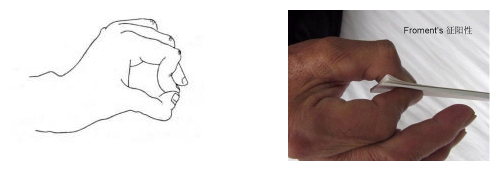

知识点6:尺神经损伤时Froment征阳性。

Froment征也叫spinner征。是尺神经损伤的表现,为拇指和食指用力对捏,但是由于拇内收无力,远端指间关节代偿性屈曲,使两者不能捏成一个圆形的"O"型。这也叫拇食指夹纸实验,由于拇内收无力,夹不住纸,轻轻一抽就抽掉了。

特别强调,我们通常所说的“夹纸实验”其实是环小指夹纸实验,索性都是尺神经损伤的表现,只要知道夹纸实验阳性是尺神经损伤表现,记住就行了,不要纠结什么手指。